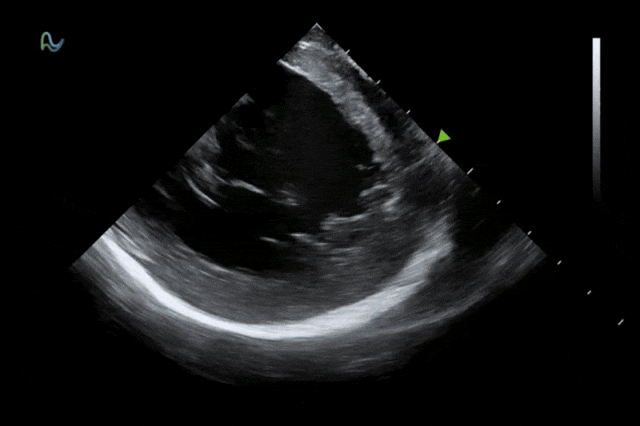

心腔內(nèi)超聲(ICE)被譽為心臟介入手術(shù)的"黃金眼",能夠通過微創(chuàng)方式實時呈現(xiàn)心臟內(nèi)部結(jié)構(gòu)和血流成像,為房顫消融、左心耳封堵、先心病介入等手術(shù)提供精準成像導航。相較于傳統(tǒng)影像手段,ICE具有無輻射、實時成像、操作靈活等顯著優(yōu)勢,已成為國際指南推薦的核心診斷技術(shù)。

本次獲批的ICE導管在全球首次采用了80陣元大孔徑高密度探頭設計,較傳統(tǒng)普通的64陣元產(chǎn)品大幅度提升了成像分辨率、成像深度和圖像對比度,可清晰辨識心臟細微結(jié)構(gòu)和血流,為復雜手術(shù)提供更可靠的超聲成像支持。同時,8F導管憑借更小的外徑,顯著提升導管通過性和操控性,對病人創(chuàng)傷更小,尤其適合血管條件受限或小心臟患者;10F導管則憑借其優(yōu)質(zhì)的成像質(zhì)量,為復雜心臟介入手術(shù)提供精準的影像引導。